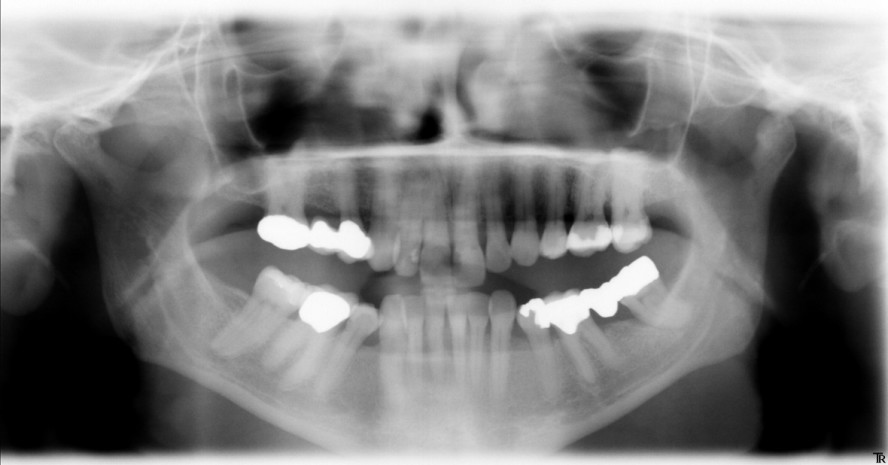

Ob tatsächlich destruktive Prozesse des marginalen Parodontiums im Rahmen bakterieninduzierter immuno-inflammatorischer Prozesse ablaufen, lässt...

Ob tatsächlich destruktive Prozesse des marginalen Parodontiums im Rahmen bakterieninduzierter...

Mit der regenerativen Parodontalbehandlung wird die Wiederherstellung des Zahnhalteapparates angestrebt. Neben Risikofaktoren ist für das Gelingen...

Mit der regenerativen Parodontalbehandlung wird die Wiederherstellung des Zahnhalteapparates...